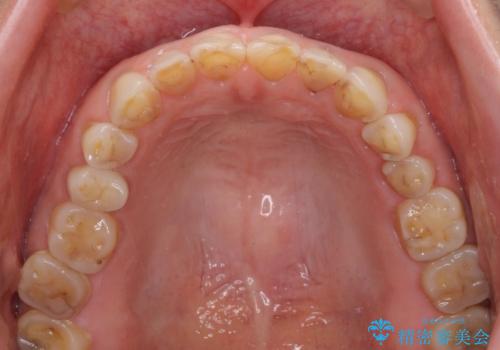

- 咬み合わせと度重なる応急処置の繰り返しにより、前歯がガタガタになってしまったとのことで来院された患者様です。

4本の前歯が気になっていたので、全てをオールセラミッククラウンにて補綴治療を行うこととしました。

4本とも治療前の歯髄の状態は正常でしたが、補綴治療により歯を大きく削ることになるため、歯髄が炎症を起こすリスクがあることを了解いただきました。